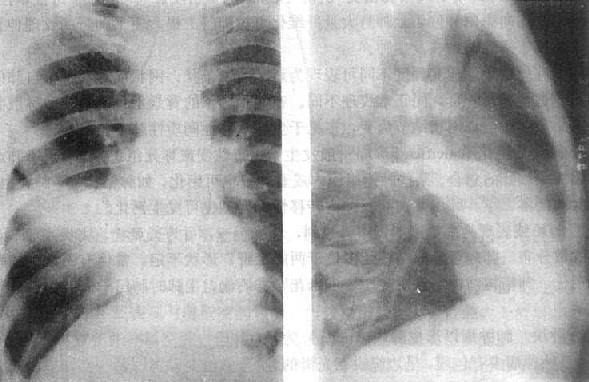

5.肿块 肺肿瘤以形成肿块(mass)为特征。肺良性肿瘤多有包膜,呈边缘锐利光滑的球形肿块,生长慢,一般不发生坏死。肺含液囊肿的X线表现与良性肿瘤不易区分,但含液囊肿可随深呼吸运动而有形态的改变。恶性肿瘤多无包膜,呈浸润性生长,故边缘多不锐利,并可有短细毛剌伸出。由于生长不均衡,其轮廓常呈分叶状或有脐样切迹(图3-1-12)。生长快,可发生中心坏死。

肺肿块

图3-1-12 肺肿块

右肺外围型肺癌,肿块呈分叶状,边缘清楚,密度均匀